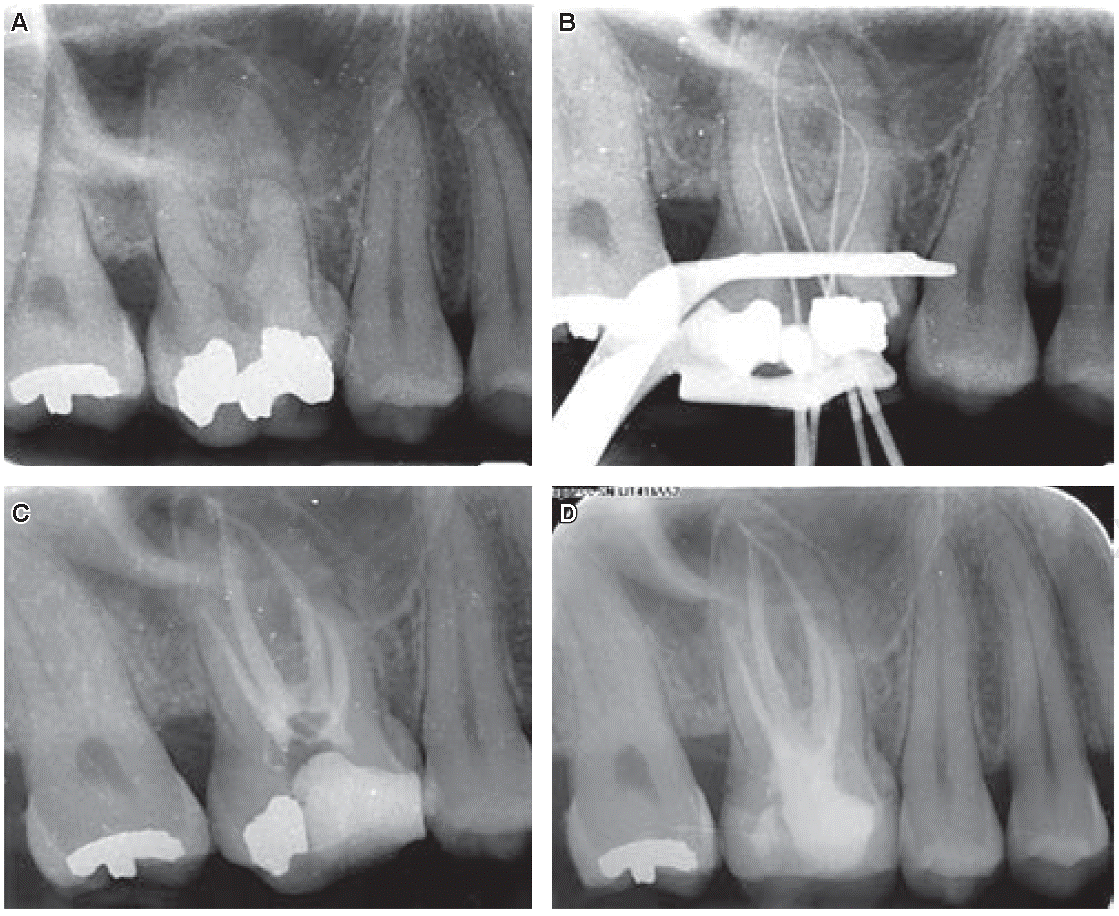

Paciente femenino de 34 años de edad, sin alteración sistémica al momento del interrogatorio, que acudió a una Clínica de Enseñanza Odontológica de la Escuela Nacional de Estudios Superiores, Unidad León de la UNAM, por referir dolor del órgano dental 16 al masticar. A la exploración clínica se observó una restauración con amalgama mal ajustada y mediante una radiografía se percibió un ensanchamiento del espacio del ligamento periodontal en la porción mesial de la raíz palatina (Figura 1A). Se realizaron pruebas de vitalidad pulpar de frío y calor, que dieron negativo, mientras que las pruebas periodontales de percusión horizontal y vertical fueron positivas, por lo que se emitió un diagnóstico de necrosis pulpar con periodontitis apical sintomática. Previo a la realización de historia clínica y obtención del consentimiento informado, se anestesió a la paciente usando solución mepivacaína al 2% con epinefrina 1:80.000 (ZEYCO, EUA). Posterior al aislamiento absoluto con dique de hule (NicTone, Romania) y grapa número ocho (Hu-Friedy, EUA) se realizó cavidad de acceso, eliminación de caries y eliminación de la restauración desajustada con fresa de carburo de bola número cuatro (Hager & Meisinger, Alemania). En la exploración del piso de la cámara pulpar se observaron cuatro conductos, se procedió a irrigar profusa y repetidamente con hipoclorito de sodio al 5% para eliminar el tejido necrótico y microorganismos. Se realizó instrumentación del sistema de conductos con el sistema Protaper Next (Dentsply Maillefer, Suiza). Se utilizó localizador de ápices Root ZX Mini de J Morita (MFG Corp., Japón) para determinar la longitud real; además se obtuvieron radiografías para corroborar que dicha longitud fuera la correcta (Figura 1B), observándose que correspondía a una nemotecnia según Álvarez 2:1 para la raíz palatina, es decir, dos conductos que inician en el piso de la cámara pulpar y a nivel apical tenían sólo un foramen. Se colocó hidróxido de calcio como medicación intraconducto y se obturó con IRM (Dentsply Maillefer, Suiza) como restauración provisional.

Figura 1 A) Radiografía inicial, paciente con diagnóstico de necrosis pulpar y periodontitis apical sintomática, B) conductometría real y evidencia radiográfica de dos conductos palatinos (2:1), C) radiografía final y tratamiento de conductos concluido, D) radio grafía de control a 12 meses.

La paciente acudió a los siete días posteriores, se anestesió, se aisló y se eliminó la restauración provisional, se irrigó y eliminó la medicación intraconducto. Se colocaron conos maestros para realizar conometría y obturación con técnica lateral modificada con ultrasonido con gutapercha Hygenic (Akron, Alemania). Por último, se recortó gutapercha con glick, se condensó y se obtuvo radiografía final (Figura 1C). Se restauró el diente con corona de disilicato de litio y se realizó un control clínico y radiográfico a un año donde se observó disminución de la lesión, y la paciente se encuentra asintomática (Figura 1D).